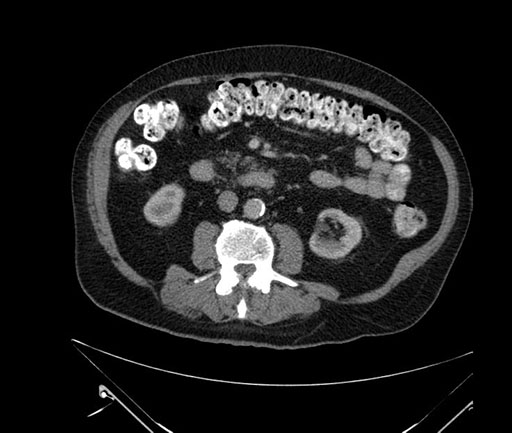

Whipple (pancreaticoduodenectomy) [case 7]

Imaging Analysis

Look through the patient's CT scan to identify any areas of concern for the necessary procedure.

Based on your CT findings, which issue(s) would give reason for "planned slowing down moment(s)" in this case?

Considering a standard Whipple procedure, what step(s) of the operation would you do differently in this case?